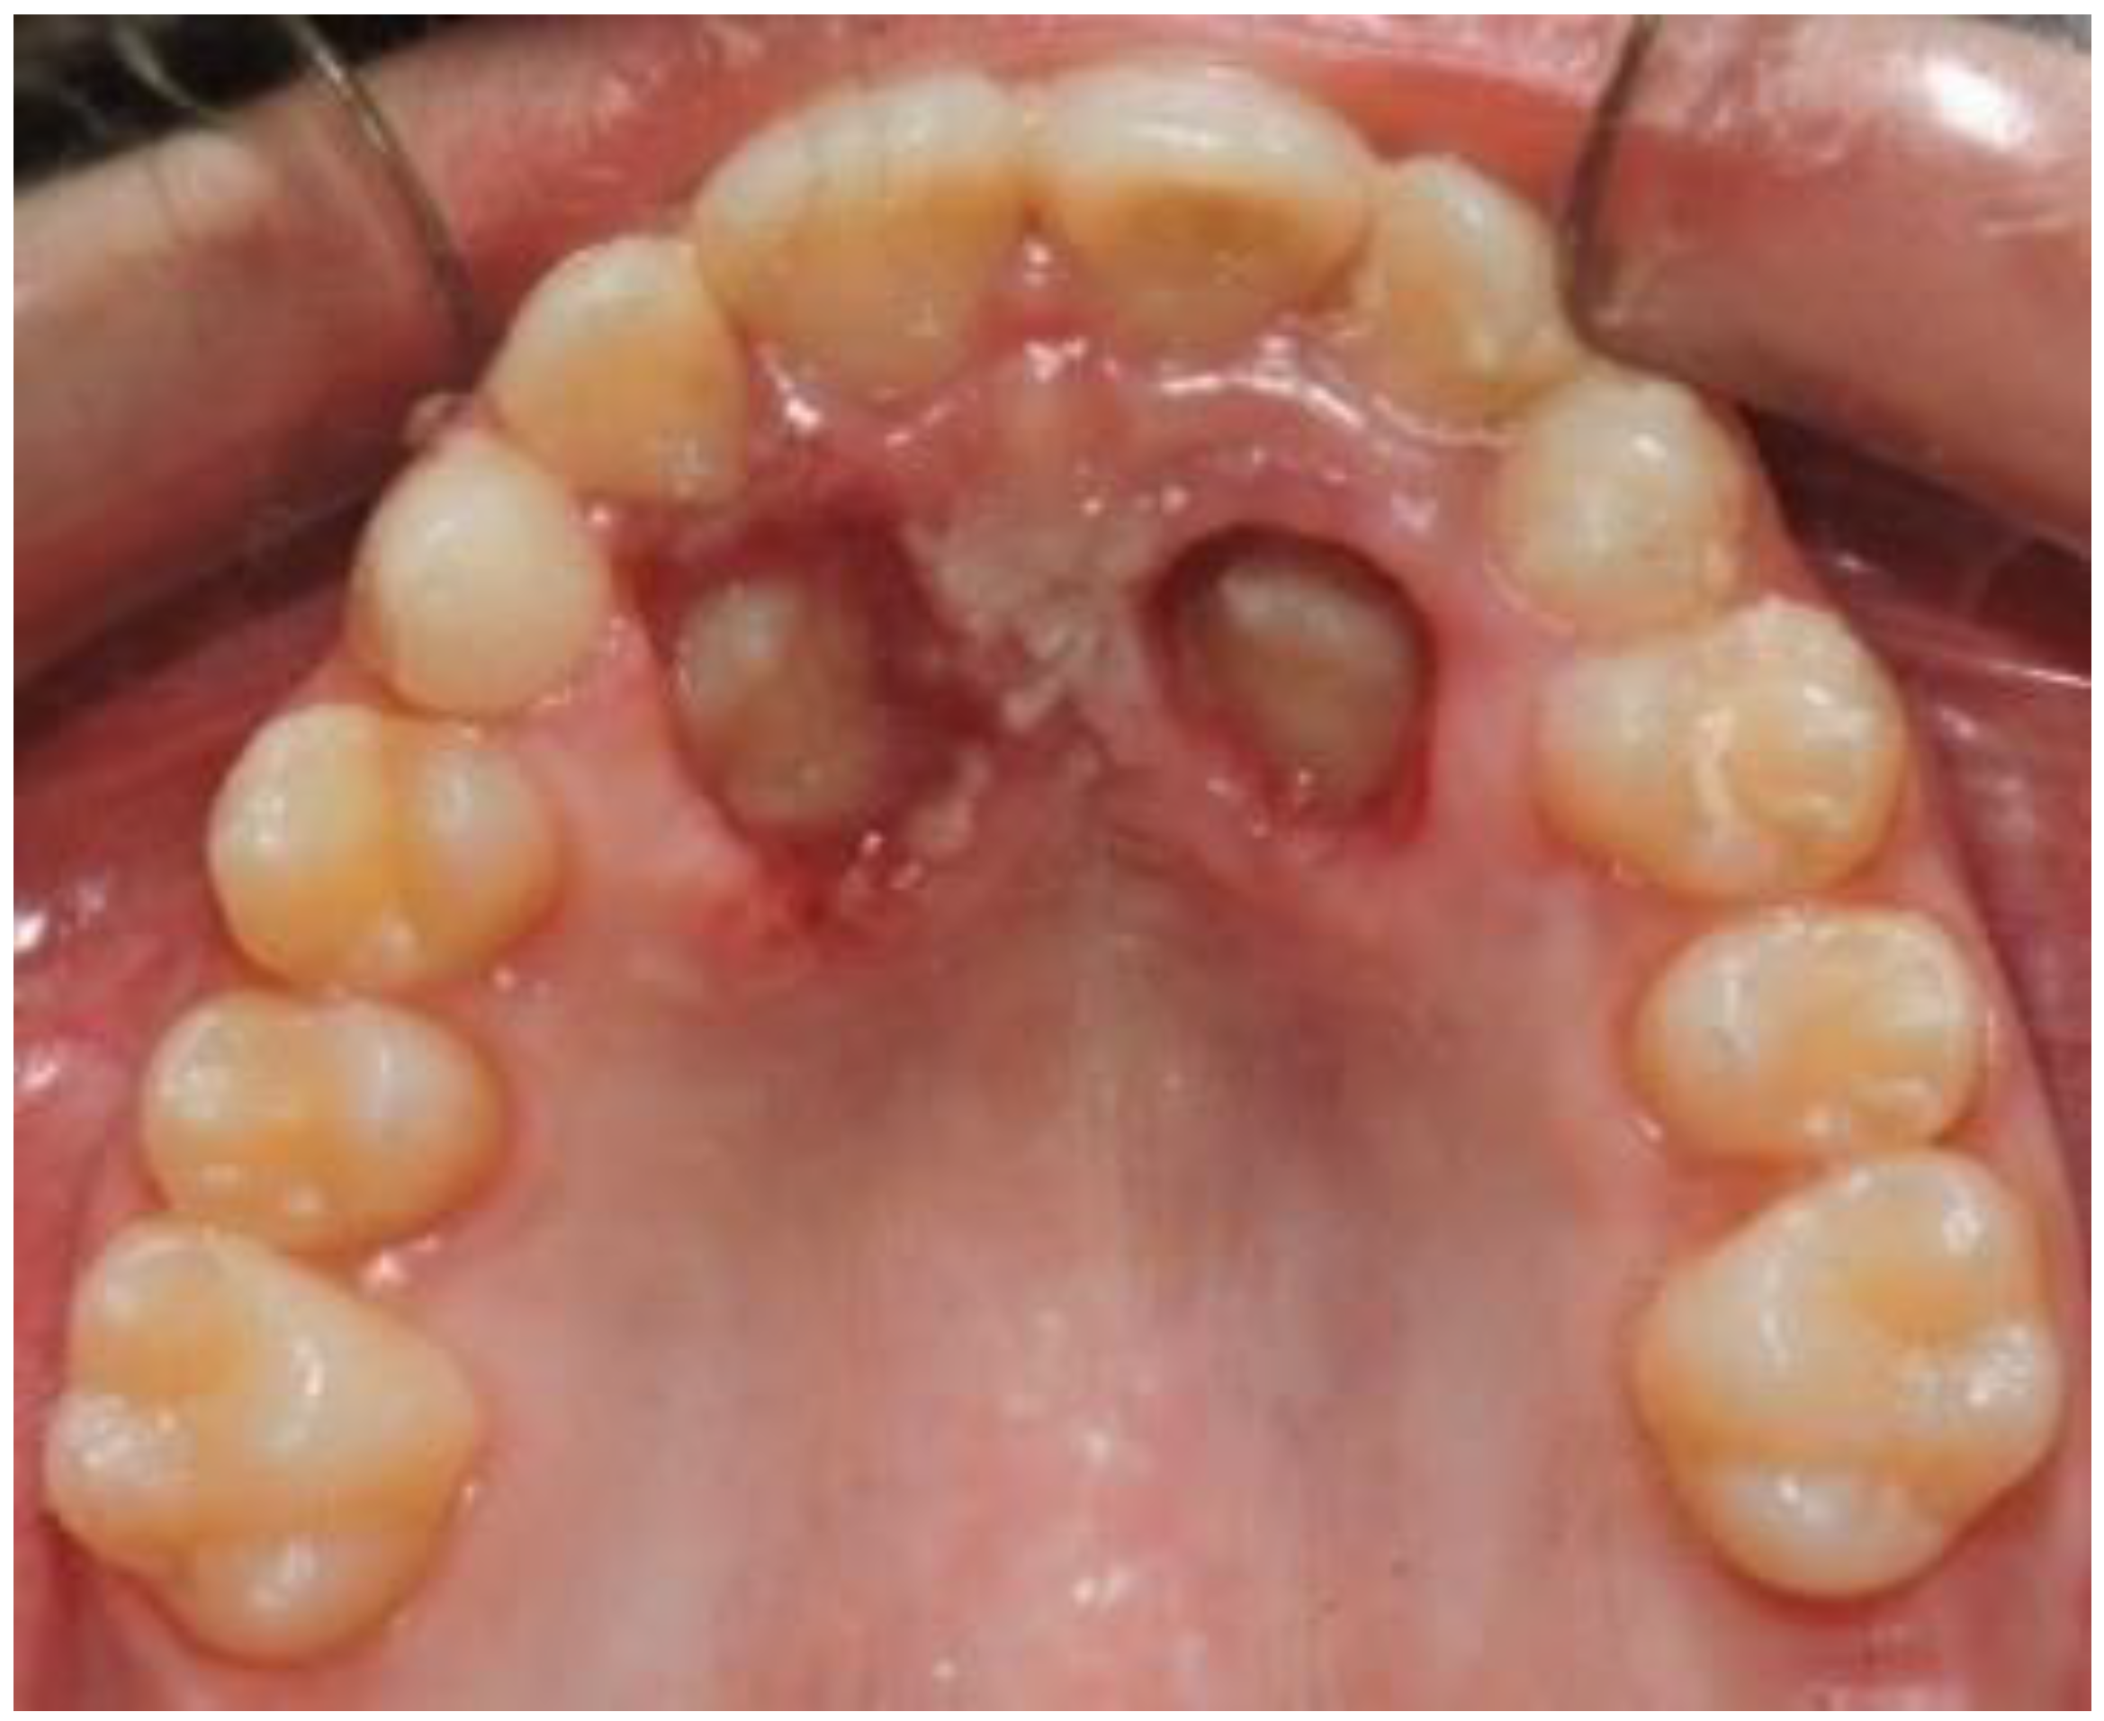

2. Case Presentation